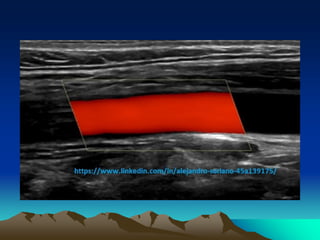

STEER

STEER: Es el área

del

Cuadrado donde se

Valora la muestra